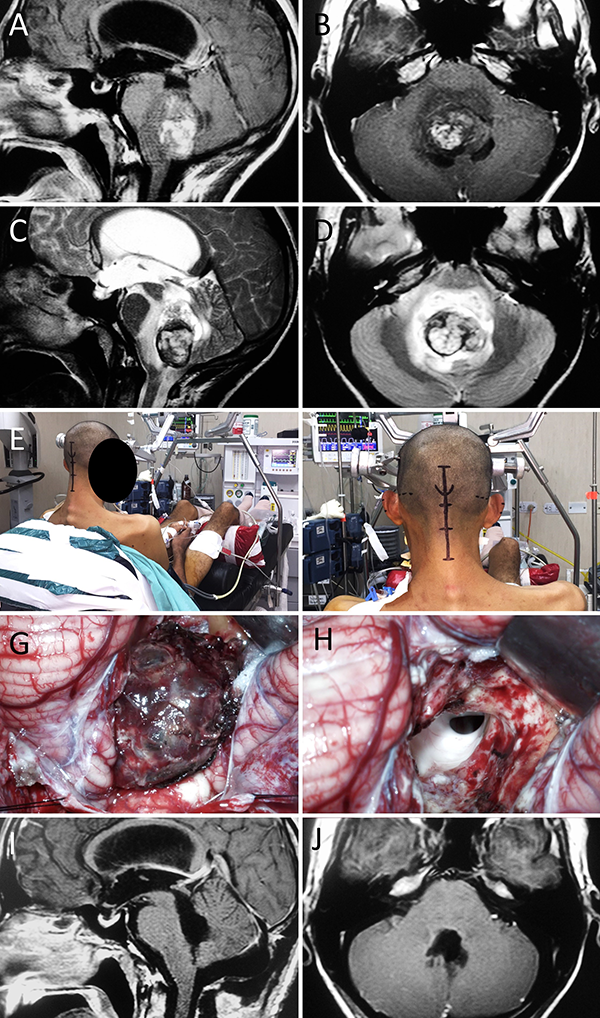

Figura 2:

Malformación de Chiari tipo I con siringomielia. A-B: RM preoperatoria; C-D: Posición; E-F: Hallazgos intraoperatorios; G-H: RM postoperatoria.

Méduloblastoma de IV ventrículo. A-D: RM preoperatoria; E-F: Posición; G-H: Hallazgos intraoperatorios. I-J: RM postoperatoria.